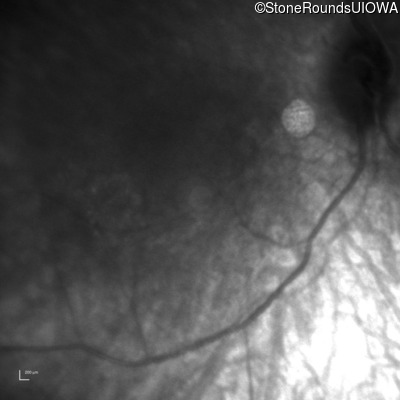

Infrared Fundus Photograph - Left -

No Light Perception

Exemplar

Expanded OCT Stack

×